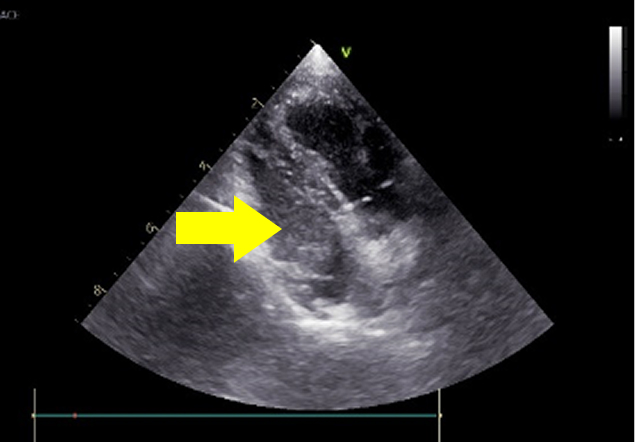

診断は身体検査、超音波検査、レントゲン検査、血圧測定、心電図、血液検査などにより総合的に行います。治療は心臓の負荷を軽減する薬による治療が一般的です。一部施設では手術による治療も行われています。(手術をご希望の方は施設をご紹介いたします)